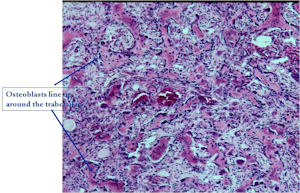

- The nidus of an osteoid osteoma consists of vascularized fibrovascular stroma and trabeculae of immature woven bone

- Nidus is sharply demarcated from surrounding reactive bone and there is an abrupt zone of transition between normal bone and the osteoid osteoma. There is no permeation of the lesion through the surrounding reactive trabeculae of bone,

- The trabeculae are uniformly lined by plump, uniform, active osteoblasts (“Osteoblastic Rimming)

- Osteoclasts may be prominent

- Mature nidus consists of more heavily calcified trabeculae of woven bone and osteoid

- No abnormal mitoses